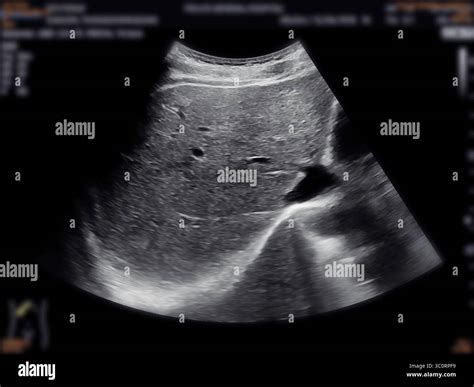

An ultrasound, also known as a sonogram, uses high-frequency sound waves to create detailed images of the organs inside your abdomen. When applied to the liver, the transducer—a small, hand-held device—emits these sound waves, which bounce off the organ and are converted into real-time images on a monitor. A normal liver ultrasound indicates that the organ appears structurally sound, with no visible abnormalities, tumors, or significant signs of disease.

This procedure is completely non-invasive and does not use ionizing radiation, making it an excellent first-line imaging tool for patients of all ages. Because it is performed in real-time, it allows the radiologist to observe blood flow, tissue density, and the presence of any structural changes immediately.

Once you are in the examination room, you will be asked to lie on an examination table, typically on your back or slightly on your left side. The sonographer will apply a clear, water-based gel to your upper abdomen. This gel serves as a conductive medium to ensure there is no air between the transducer and your skin, which would disrupt the sound waves.

The sonographer will firmly press the transducer against your skin, moving it back and forth to capture different angles of the liver. You may be asked to hold your breath for short periods to help keep the organ stable while the images are being captured. The entire process is painless and typically lasts between 20 to 40 minutes.